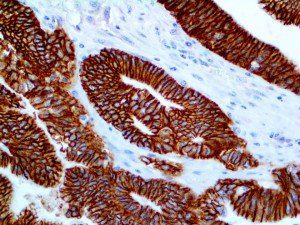

The first cytokines released are interleukin 1β (IL-1β) and tumor necrosis factor-α (TNF-α), which attract a variety of circulating white blood cells (WBCs) to the infection site, including neutrophils, monocytes, macrophages, and natural killer (NK) cells. This response, along with the antipathogenic chemicals released by these cells (i.e., complement), comprise the innate immune response. These cells directly attack the invading pathogen and also release additional cytokines, chief among them interleukin-1 and 6 (IL-6). IL-6 is essential for invoking the adaptive immune response, which calls T-cells, B-cells, and T helper (Th) cells to the infection site. IL-6 also stimulates further recruitment, proliferation and activation of macrophages.

This activation induces inflammatory monocytes to highly express IL-6, starting a localized and then systemic cascade effect that results in hyperproduction of IL-6, which accelerates the inflammatory process. Because IL-6 also increases vascular permeability, excessive levels cause blood vessels to become very leaky. This, along with clotting factors released from vascular endothelial cells, stimulates the coagulation cascade, resulting in microthrombosis (tiny clots), which leads to ischemia and tissue death of the kidney, intestines, heart, liver, brain and extremities.